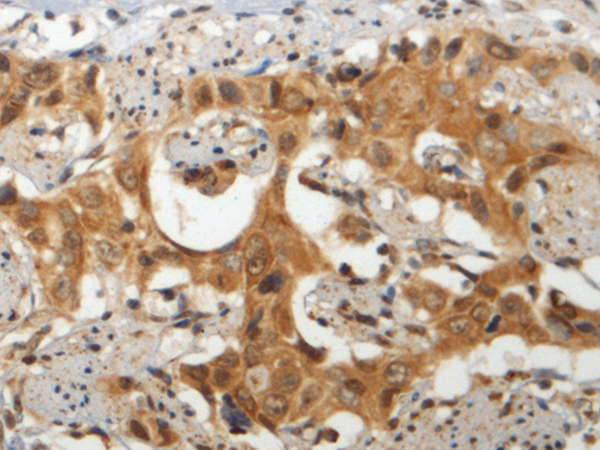

IHC positive control: |

Human esophagus cancer |

IHC Recommend dilution: |

150-300 |